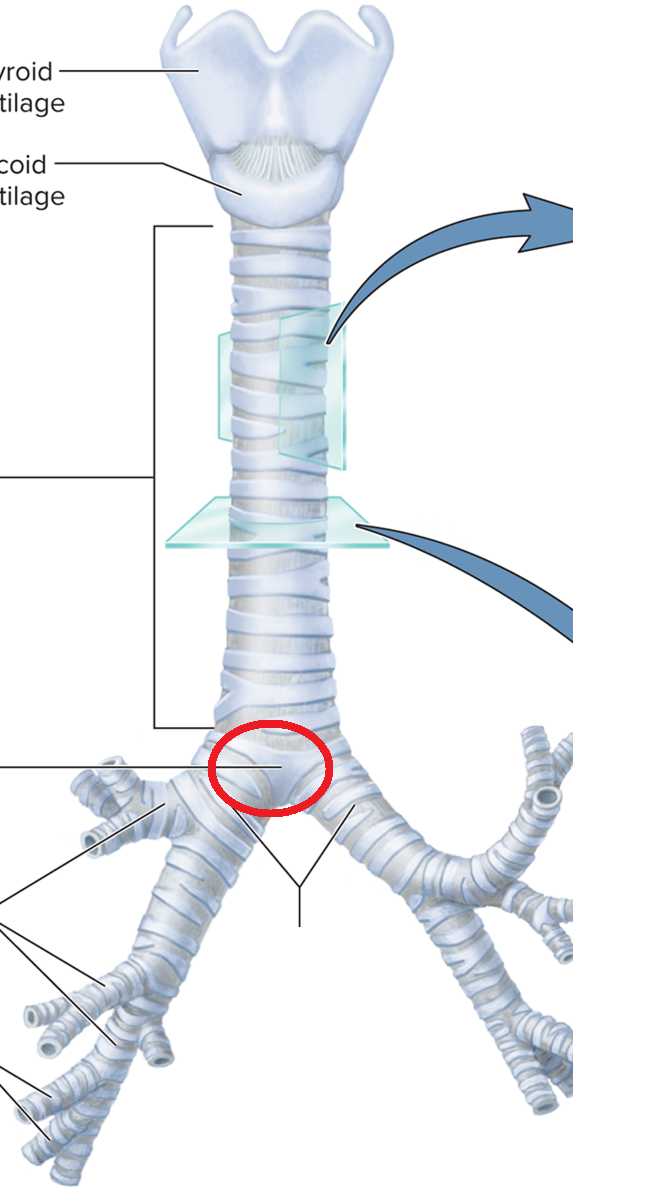

Trachea and Bronchial Tree

Carina T

Tracheal bifurcation T

Main bronchi BT

Lobar bronchi BT

Segmental bronchi BT

Bronchiole BT

Terminal bronchiole BT